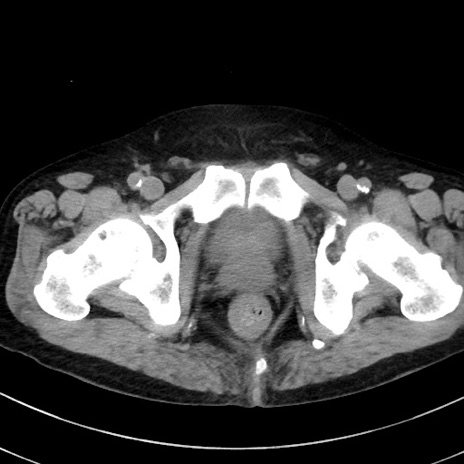

冠状断像

【症例】70歳代 男性

【主訴】腹痛・嘔吐

【現病歴】昨晩より、嘔吐・腹痛あり。今朝になっても嘔吐あり。来院。

【既往歴】心臓バイパス手術、開腹胆摘、腸閉塞

【身体所見】BP 107/71mmHg、HR 116/min、腹部:平坦、軟、下腹部に軽度圧痛あり。反跳痛なし。

【データ】WBC 15100、CRP 0.32